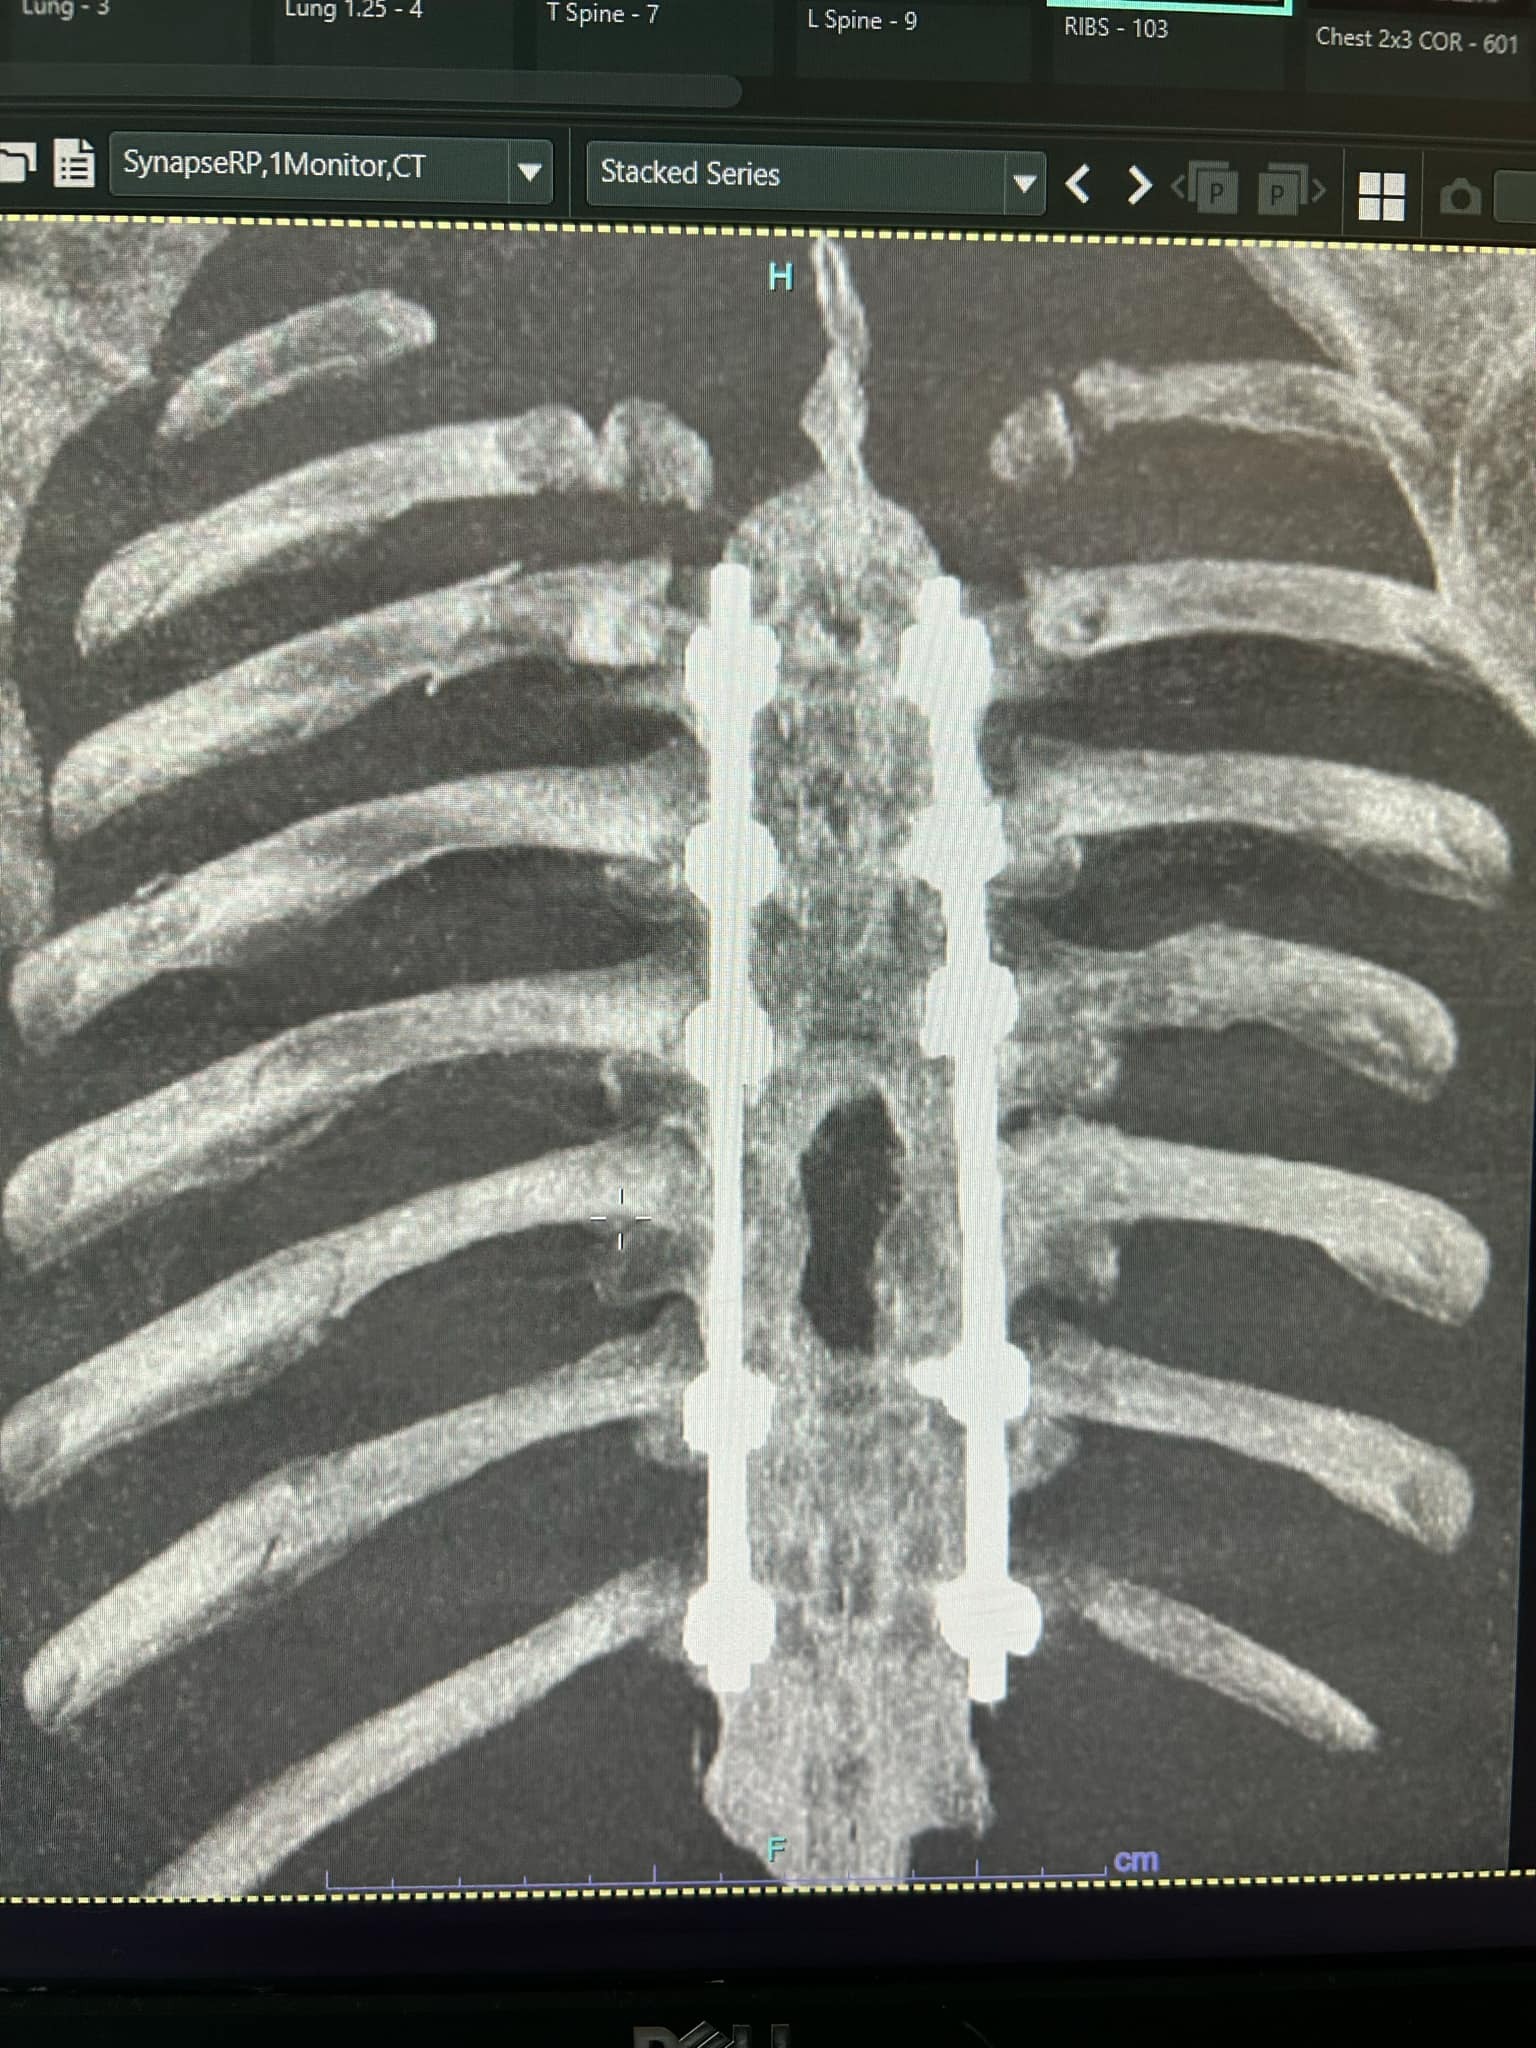

On April 28th, my partner Erick was in a serious mountain biking accident. He suffered a burst fracture in his spine (T1), a shoulder broken in three places, and eight fractured ribs. He’s already undergone emergency spinal surgery (a four-level fusion), and the recovery ahead will be long and intense—expected to take at four to six months, with physical therapy, follow-up scans, and a lot of healing time at home.